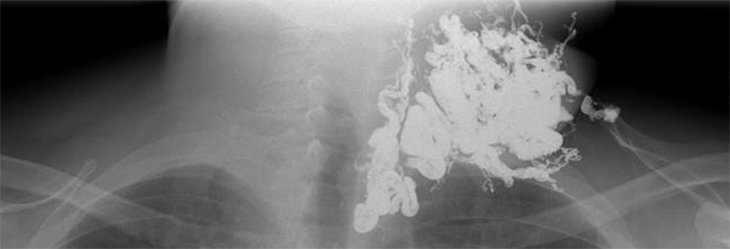

Die Behandlung von angeborenen Gefäßfehlbildungen am Universitätsklinikum Münster erfolgt in enger Zusammenarbeit der Klinik für Radiologie mit der Abteilung für Kinderchirurgie sowie der Klinik für Mund-Kiefer-Gesichtschirurgie. In einer gemeinsamen Spezialsprechstunde werden Patient*innen mit Gefäßanomalien durch alle erforderlichen Disziplinen untersucht und eine entsprechende Diagnostik wird eingeleitet. Für die nicht-invasive Diagnostik stehen in der Klinik für Radiologie sämtliche erforderlichen Geräte (Ultraschall, Magnetresonanztomographie, ggf. Röntgen) zur Verfügung. Die Therapie der Gefäßanomalien erfolgt im Anschluss entweder operativ, mittels Laser-Therapie oder bildgesteuert mittels minimal-invasiver Katheterverfahren.